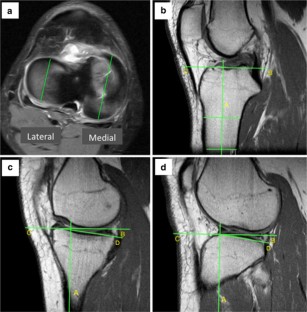

Fig. 1

Fig. 2

Fig. 3

Fig. 4